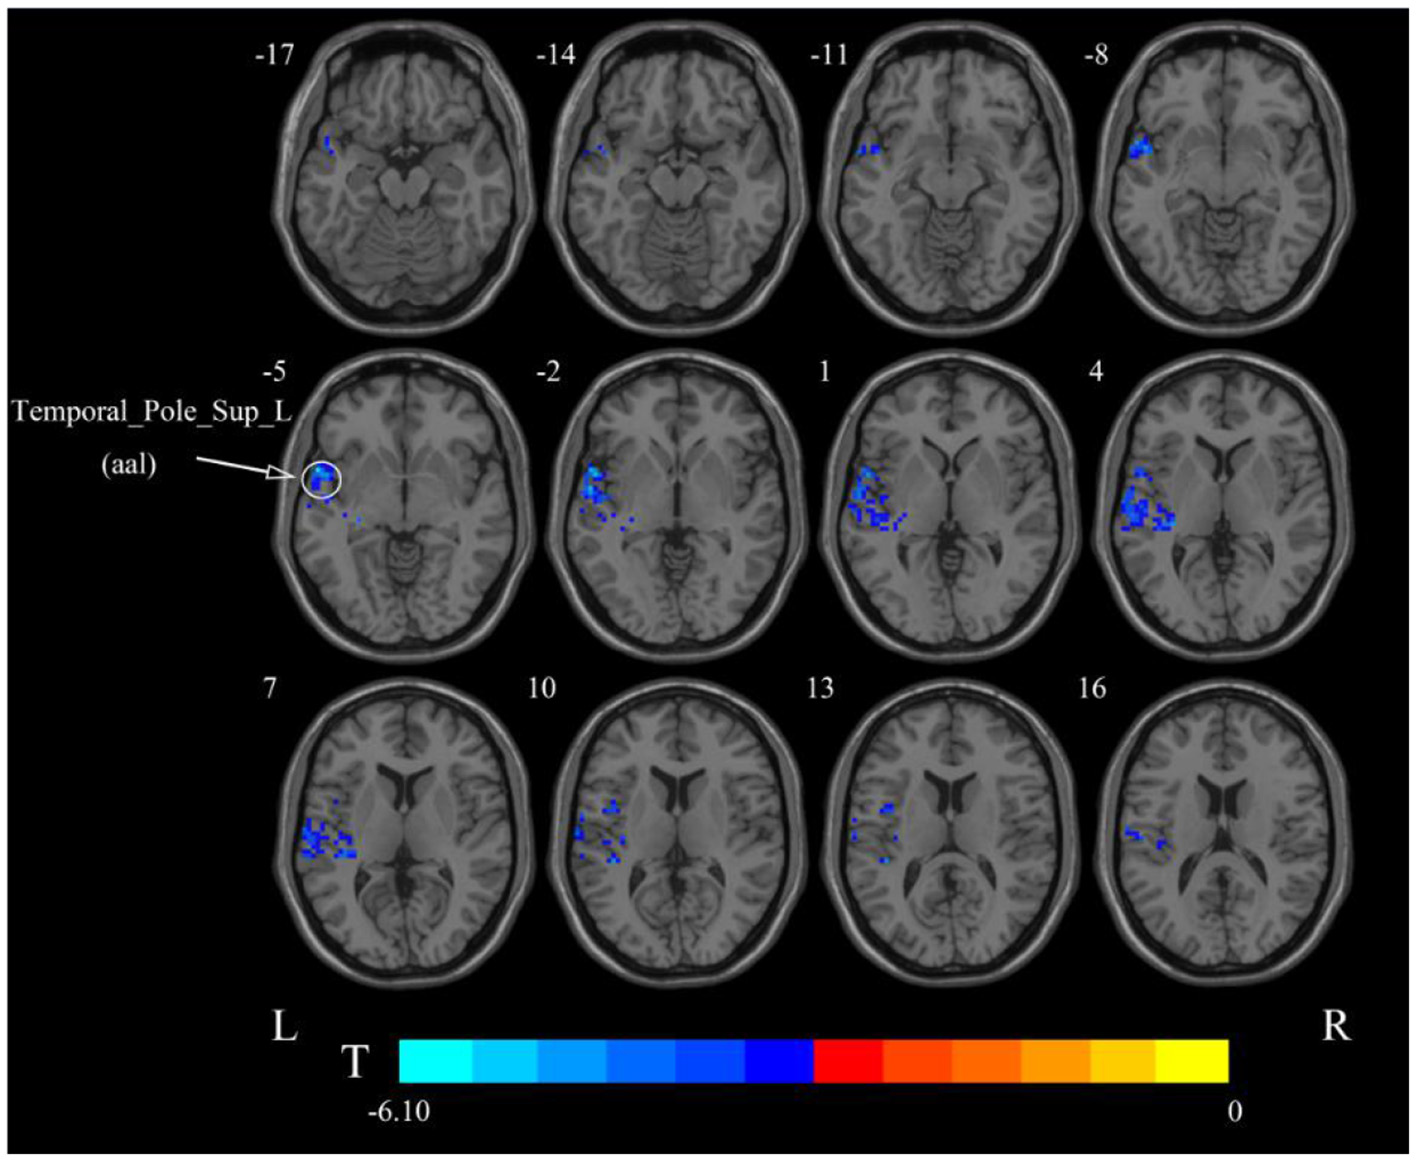

After cerebellar stimulation, in the classical frequency band we found that ALFF was significantly elevated at the pons, right cerebellum, and medulla and significantly reduced at the left temporal lobe (p < 0.05; Figure 3 and Table 1), indicating that unilateral cerebellar stimulation can produce increased spontaneous neural activity in the cerebellum and brainstem and suppress activity at the contralateral temporal lobe. In addition, we found that ALFF at the left temporal lobe was also decreased in the slow-4 band and slow-5 band (p < 0.05; Figures 4, 5 and Table 1).

Figure 4. Statistical maps showing ALFF change pre- and post-rTMS in the slow-4 band. Cool colors showing ALFF decreased after rTMS p < 0.05.